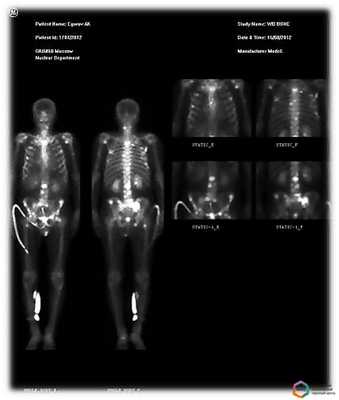

Остеосцинтиграфия - метод диагностики, основанный на введении в организм пациента препарата, который быстро и легко накапливается в костной ткани и содержит в своем составе изотоп (общее название - радиофармпрепарат). Вспышки излучения, который испускает изотоп, фиксируются затем с помощью специальной гамма-камеры. Этот метод позволяет изучить сразу весь скелет в отличие от рентгеновских снимков, на который имеется изображение отдельных костей. Остеосцинтиграфия является основным способом ранней диагностики первичных опухолей и метастатических поражений скелета, оценки эффективности проводимого лечения после химиотерапии и лучевой терапии злокачественной опухоли, а также дифференциальной диагностики опухолевого и воспалительного поражения костей.

Суть метода состоит в том, что пораженая костная ткань накапливает радиоактивные изотопы гораздо быстрее, чем здоровая. В итоге на изображениях паталогическиеочаги в костях будут иметь вид зонповышенного или пониженного накопления (черный и белый цвет). Отмечено, что метастазы могут быть обнаружены с помощью остесцинтиграфии значительно раньше, чем при выполнении других исследований.

Подготовка не требуется, исследование проводится в двух проекциях, передней и задней в режиме всего тела, через 2 - 2,5 часа после внутривенного введения препарата.Перед исследованием пациенту внутривенно водят небольшую дозу радиофармпрепарата, содержащего изотоп технеция Тс99 и способного накапливаться в костной ткани, затем оценивают его распределение с помощью гамма-камеры и серии сцинтиграмм.